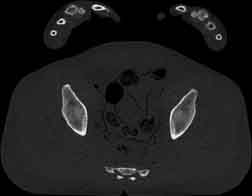

Visible Human male: Sectio transversalis 1841

CT

NMR

Pd                          / T2 \                         T1